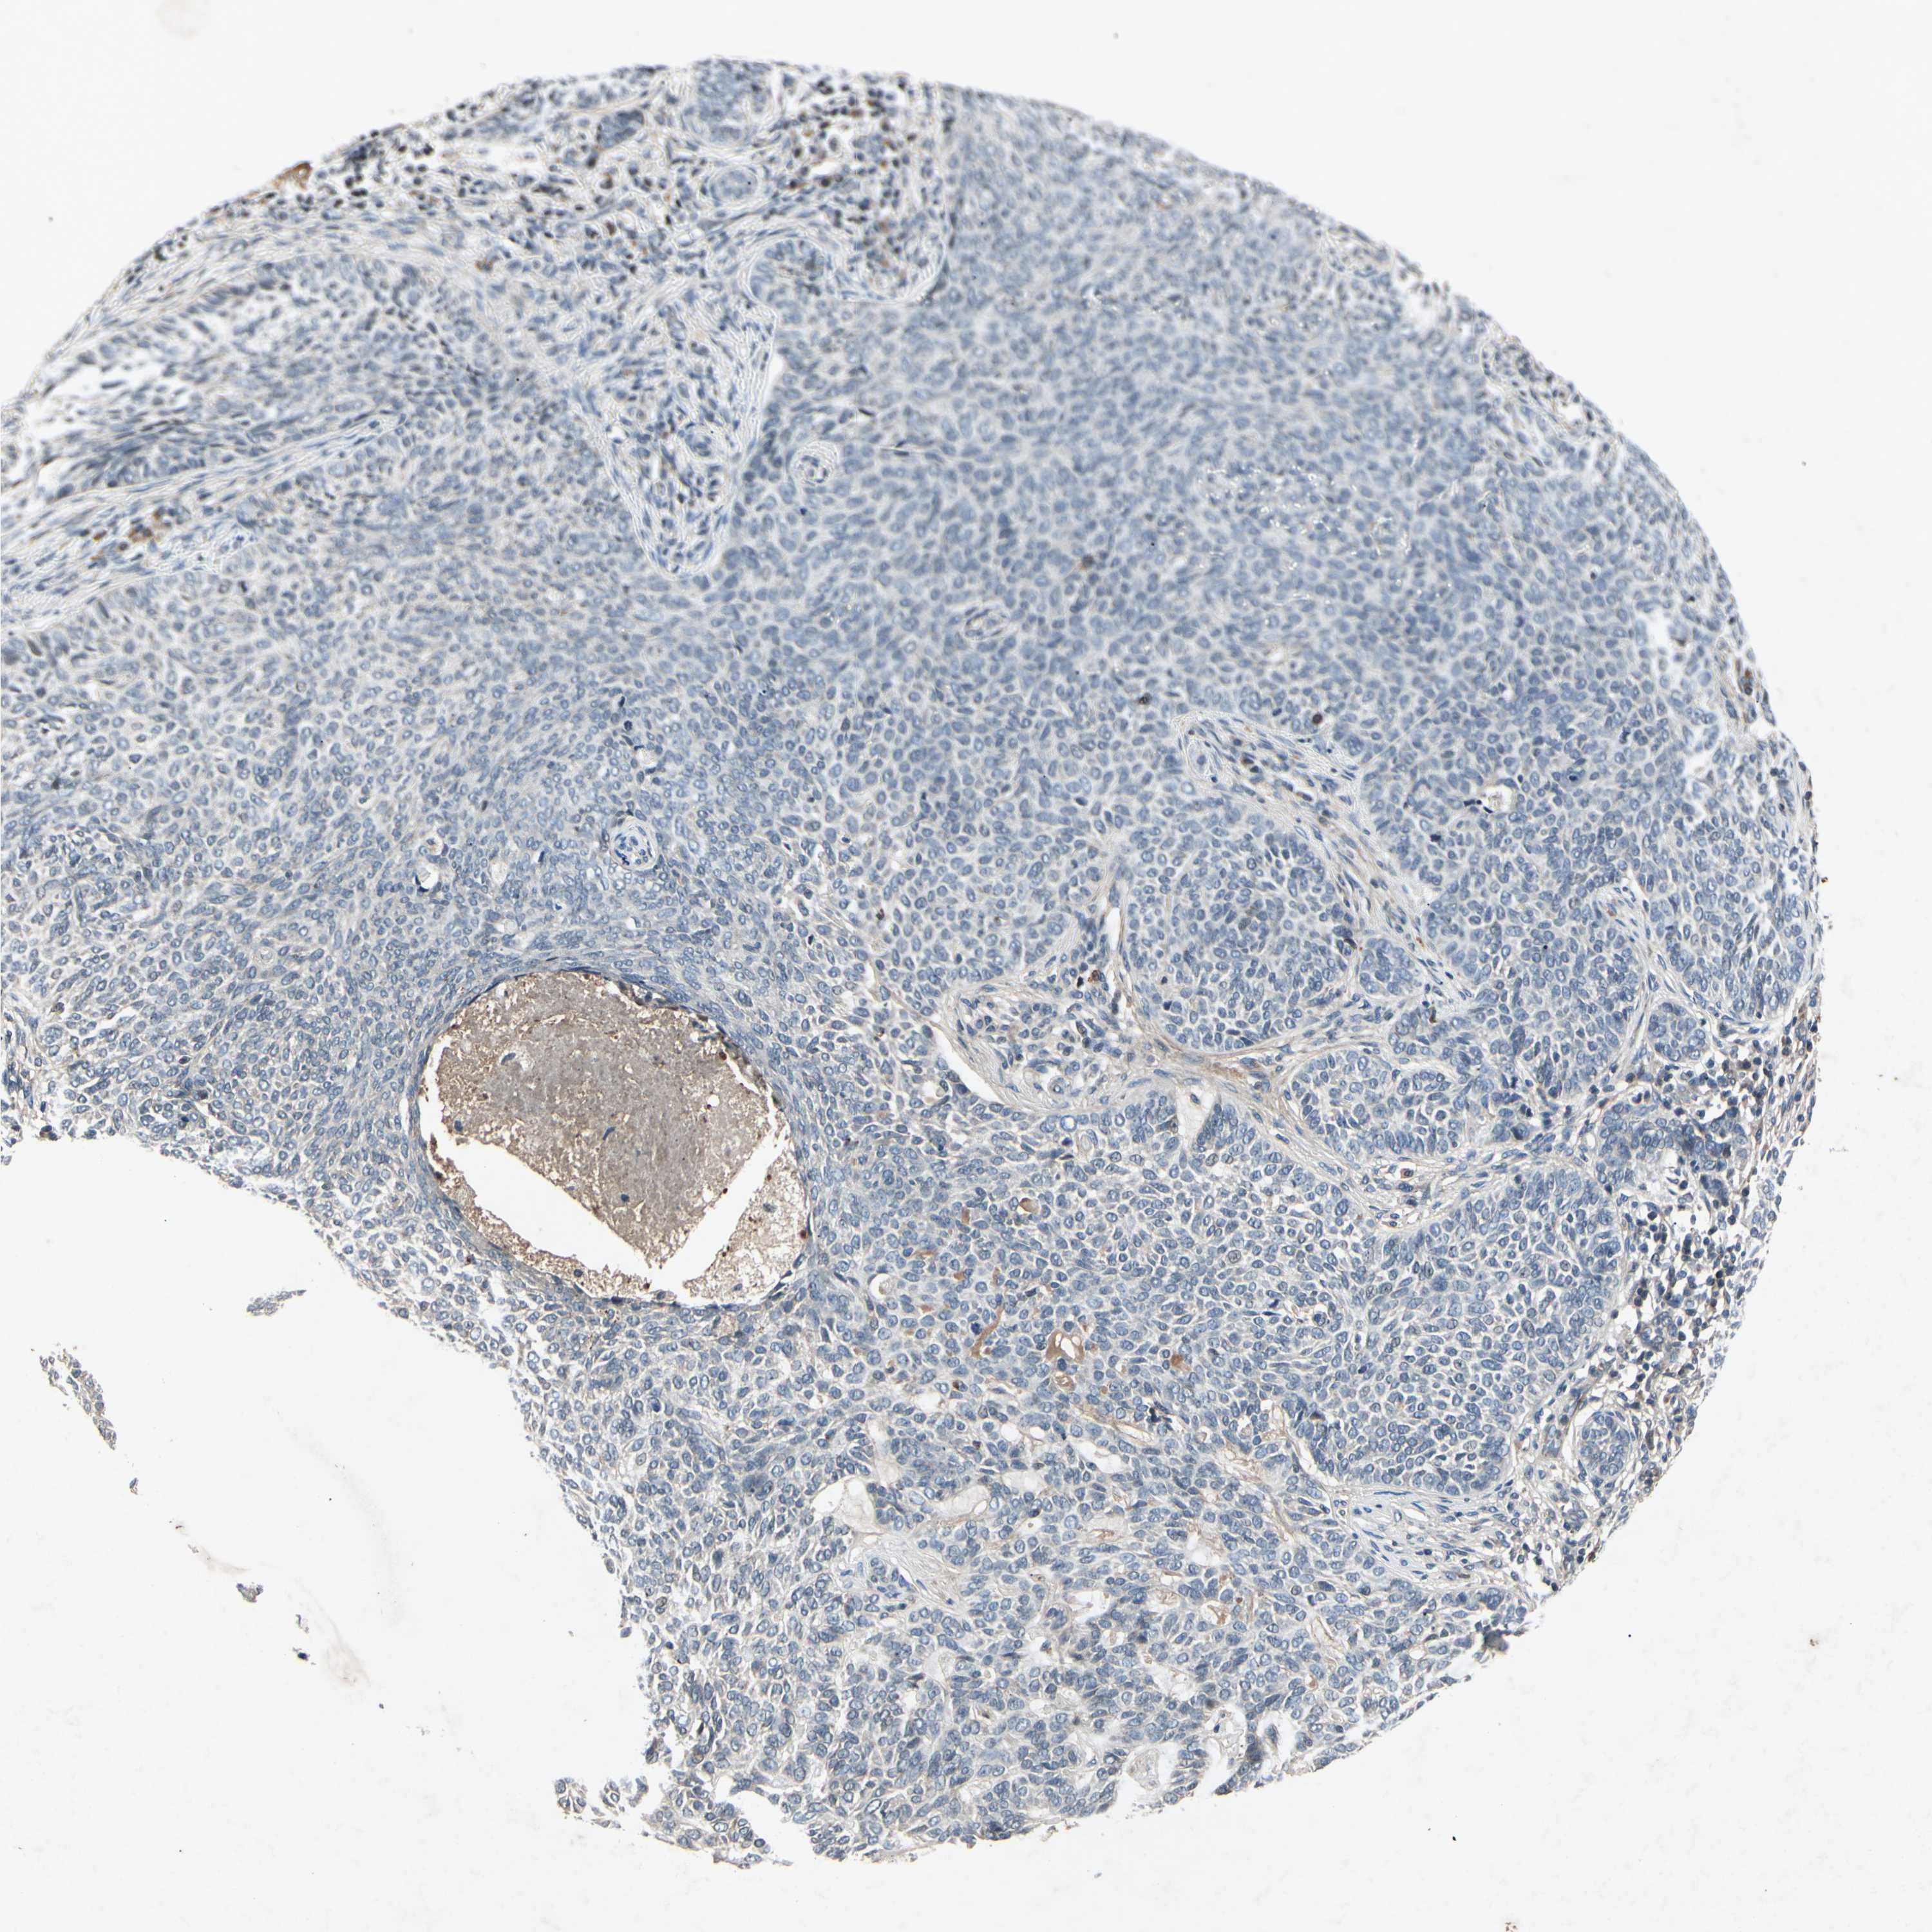

CANCER SKIN CANCER Show tissue menu

SKIN CANCER - Protein expressioni

A mouse-over function shows sample information and annotation data. Click on an image to view it in a full screen mode. Samples can be filtered based on level of antibody staining by selecting one or several of the following categories: high, medium, low and not detected. The assay and annotation is described here.

Antibody stainingi

Antibody staining in the annotated cell types in the current human tissue is reported as not detected, low, medium, or high, based on conventional immunohistochemistry profiling in selected tissues. This score is based on the combination of the staining intensity and fraction of stained cells.

Each image is clickable and will lead to virtual microscopy that enables deeper exploration of all samples and also displays staining intensity scores, fraction scores and subcellular localization as well as patient and tissue information for each sample.

Antibody HPA063595

Antibody HPA064970

Antibody CAB009966

Staining

High

Medium

Low

Not detected

Basal cell carcinoma

Squamous cell carcinoma, NOS